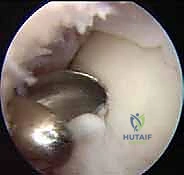

المرحلة الثانية: جراحة الزراعة (Implantation)

بمجرد أن تصبح الخلايا جاهزة، يعود المريض لإجراء الجراحة الرئيسية.

1. الوصول إلى المفصل: تُجرى هذه العملية عادة كجراحة مفتوحة صغيرة (Mini-open) أو في بعض الأحيان عبر المنظار (حسب موقع الآفة). قد يتطلب الوصول إلى بعض الآفات العميقة إجراء قطع عظمي مؤقت (Osteotomy) في الكعب الإنسي (Malleolus) للوصول للآفة، ثم يتم إعادة تثبيته بمسامير طبية في نهاية العملية.

2. تحضير السرير العظمي: يقوم الدكتور هطيف بإزالة جميع الأنسجة الغضروفية الميتة والعظم المتصلب وصولاً إلى الحواف السليمة والصحية للغضروف والعظم، لإنشاء بيئة دموية مثالية لاستقبال الخلايا.

3. زراعة الغشاء الخلوي: يتم قص الغشاء الكولاجيني المشبع بملايين الخلايا الغضروفية الخاصة بالمريض ليتطابق تماماً مع حجم وشكل الآفة.

4. التثبيت: يُثبت الغشاء في مكانه باستخدام لاصق حيوي طبي (Fibrin Glue) وأحياناً غرز دقيقة جداً قابلة للامتصاص.

5. الإغلاق: يتم إغلاق الشقوق الجراحية بعناية فائقة، ووضع الكاحل في جبيرة أو حذاء طبي لحمايته.